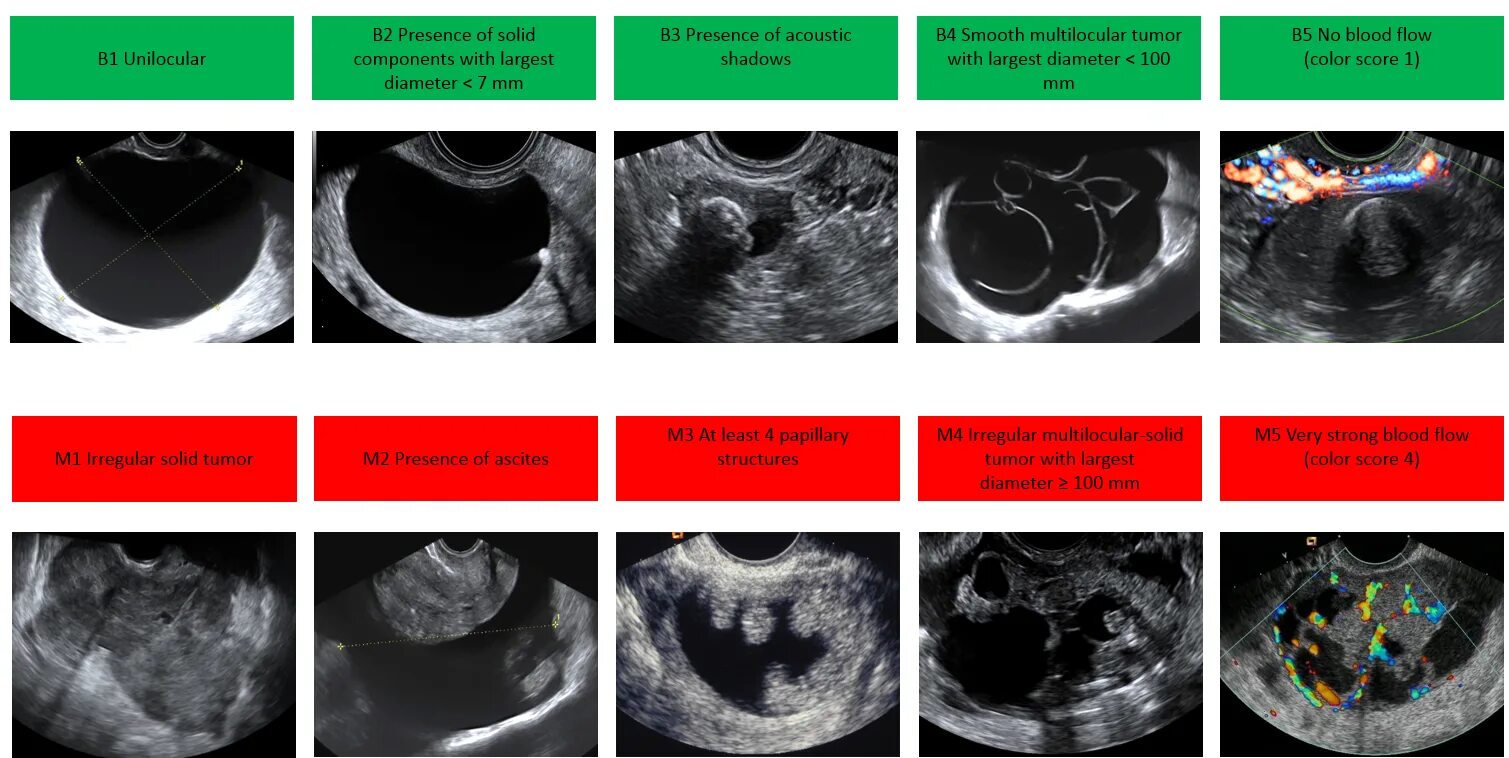

Классификация яичников